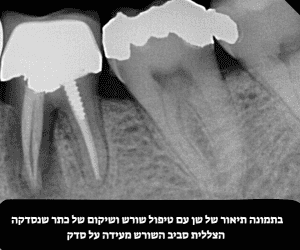

| סדק עמוק עד המוך | טיפול שורש + כתר ביום אחד |

| סדק שמגיע עד שורש השן | צילום CBCT לאבחון –

לרוב לא ניתן להציל את השן – עקירה |